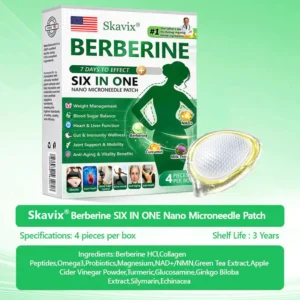

Pain-Free Active Delivery

Each needle is0.27mmlong, just1/7the thickness of a hair, and made from a dissolvable medication. These microneedles are precision-engineered using the latest manufacturing techniques to ensure a seamless, pain-free experience while effectively delivering active ingredients directly into the skin.